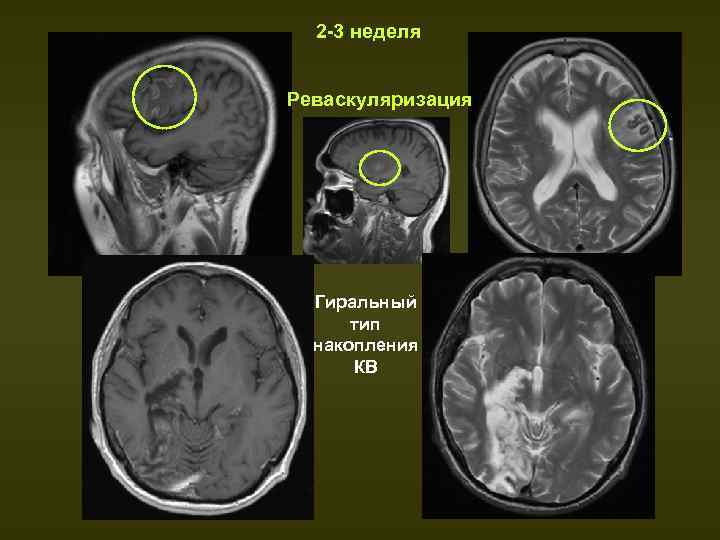

Умеренное накопление контраста

Умеренное накопление контраста 112 фото